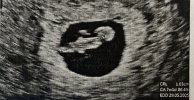

No cóż… u mnie trzecia ciąża, duże zaskoczenie , mam 41 lat a mąż 43. Moja pierworodna ma ciężką wadę serduszka na tle genetycznym , ktore w żadnym z badań prenatalnych nie zostało wykryte więc u mnie strach jest ogromny , o wszystko .Witam. Jestem tu nowa i myślę że się tu odnajdę. Czytałam dużo forum i tak trafiłam na tą stronę. Chciała bym komuś się wygadać odnośnie mojej sytuacji może któraś z was tak miała i będzie umiała ocenić moja sytuację. Jestem mama 3 dzieci córka 10lat córka 6 i synek 9 a zaraz 10 miesięcy. Ostatnio byłam u lekarza i okazało się że znów rodzina nam się powiększy. Powiedzcie czy to źle że się nie cieszę z tego bo obawiam się o najmłodsze dziecko że nie poświęcę mu tyle czasu ile powinnam? Niewiem czy dobre forum ale warto próbować. Aktualnie jestem w 8 tyg ciąży i bardzo się boję. Pozdrawiam